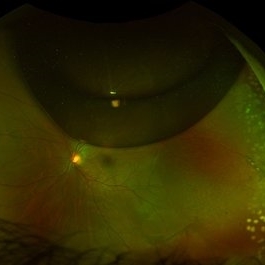

Chronic Retinal Detachment after Pneumatic Retinopexy

This is a fundus photo in the eye of a young phakic patent who presented with a 6 month history of "difficulty seeing at night" and subjective nasal "blurriness" in the left eye. There was a chronic temporal RD, OS, extending to the arcades (Mac on). This photo is week 1 s/p Pneumatic retinopexy with SF6 gas and laser retinopexy to temporal breaks (6 holes, lattice); no PVD. As you can see, there is a "bleb" of viscous schlieren given the chronic nature of this RD that persist posterior to the breaks and temporal to the macula. This type of sub retinal fluid may take months to years to resorb.

Condition/keywords: chronic retinal detachment, pneumatic retinopexy